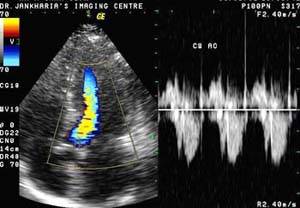

2D

Echo – Two Dimensional Echocardiography |

Q1. How is it performed?

A. The echocardiogram will be performed

and recorded by a specially trained cardiologist.

It usually takes approximately one-half hour. Since

the transducer must be placed directly on the chest

wall or upper abdomen, you will be asked to disrobe

from the waist up.